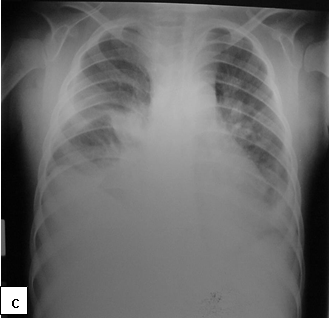

Clinical presentation:Cutaneous lesions are the most common manifestations of KS, presenting as non-tender, purplish and indurated lesions. KS may also involve the lymph nodes, oral mucosa and the lungs. Visceral dissemination can occur, occasionally without skin lesions.

Figure 165a, b and c: Kaposi sarcoma involving the skin, lymph nodes and lungs (Courtesy of Dr George Chagaluka, Queen Elizabeth Central Hospital, Malawi).